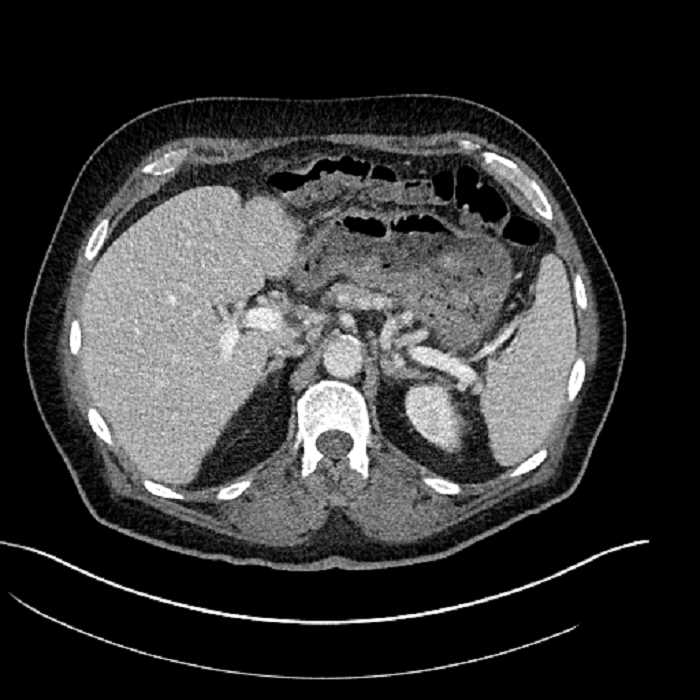

Age: 63

Sex: Male

Indication: Abdominal pain

• Large fluid density structure in hepatic segments 7 and 8 measuring 10 x 7 x 7 cm with internal septation and circumferential ill-defined low density compatible with edema

• Peripherally enhancing subcapsular collections along the anterior margin of the left hepatic lobe measuring 3 x 1 cm and 2 x 1 cm

• Clearly marginated fluid density structure in segment 7 and several other scattered tiny hypodensities, which likely represent cysts

• Hepatic abscess

Acute sigmoid diverticulitis complicated by a small contained perforation and a large abscess in the right hepatic lobe. Additional small subcapsular abscesses along the anterior margin of the left hepatic lobe.

• The classic CT imaging appearance is a double target sign with internal low density surrounded by an internal enhancing rim (capsule) and a low density external rim (edema)

• Abscesses may be unilocular or multilocular

• Gas is present in a minority of cases

• Unfortunately, necrotic tumors can have an overlapping imaging appearance, so it is important to follow these to resolution

Hepatic abscess showing the double target sign with low density internally surrounded by a thin inner enhancing rim (red arrow) and ill-defined outer low density rim (yellow arrow). Blue arrow indicates an internal septation. Red arrows: additional smaller subcapsular abscesses. Red arrow: focal contained perforation associated with diverticulitis.